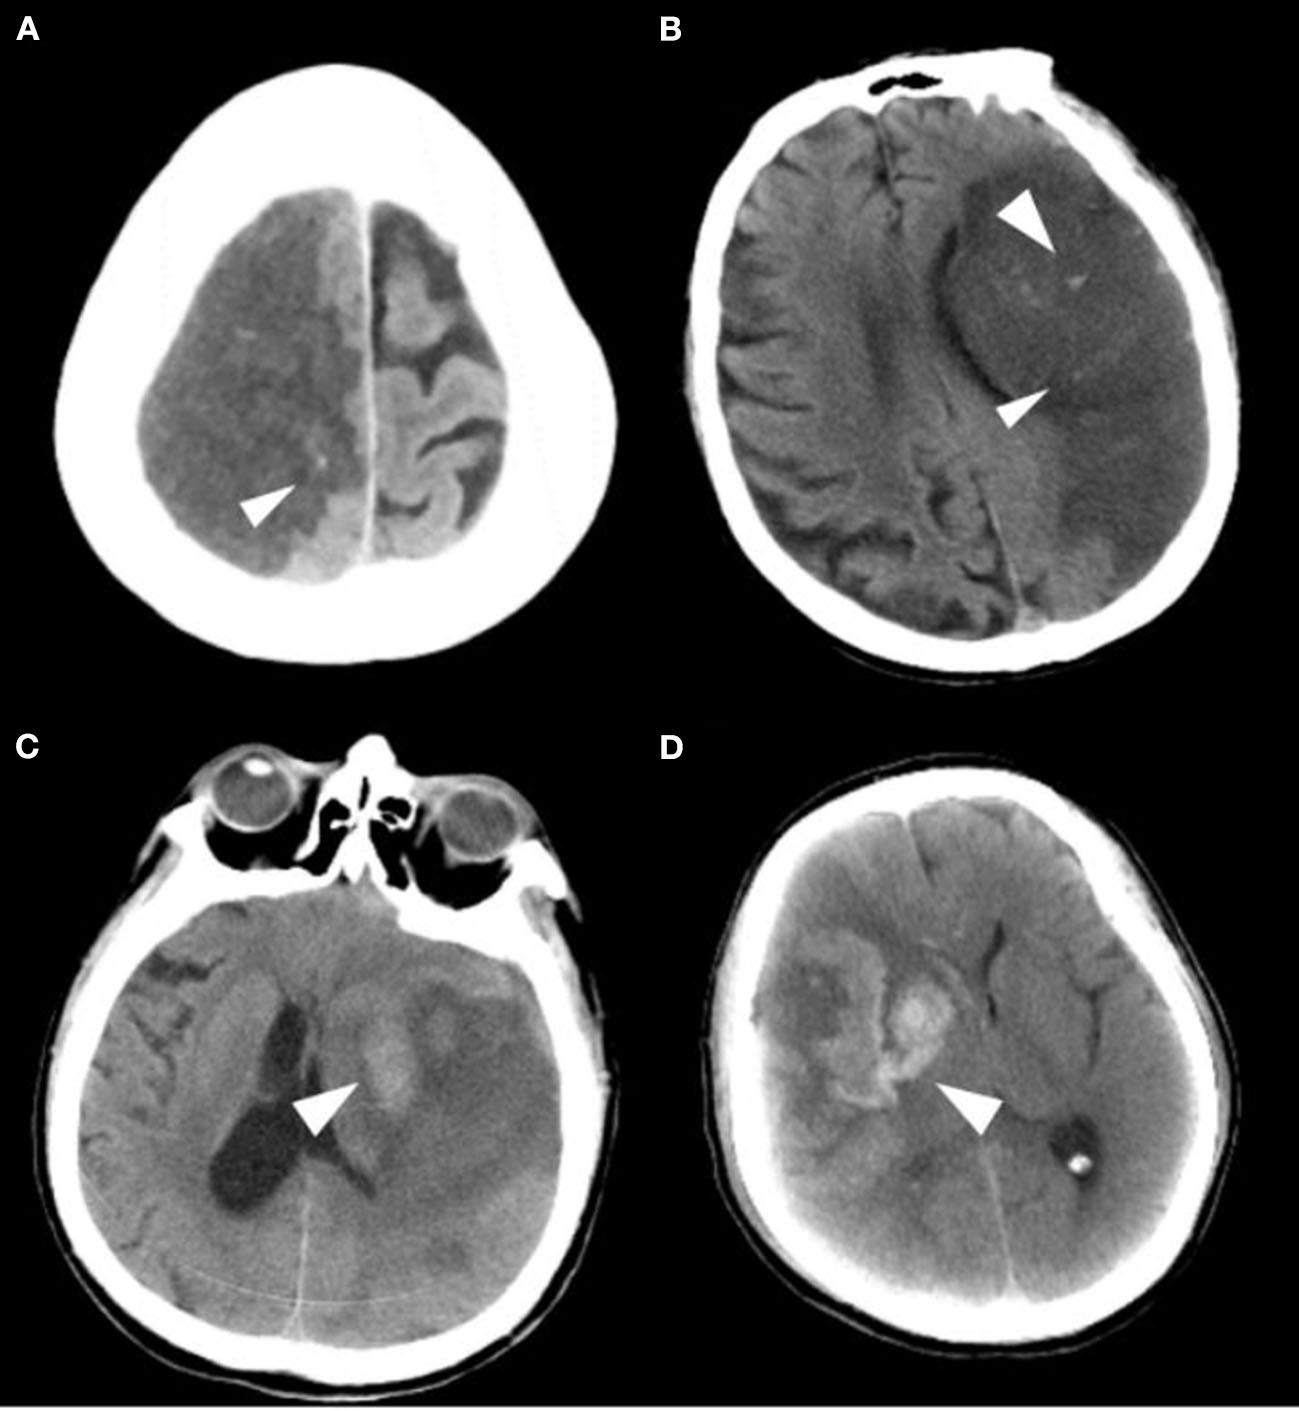

The primary safety outcome was the development of any intracranial hemorrhage events during hospitalization [as defined by the ECASS (9) criteria: HI1, hemorrhagic infarction type 1; HI2, hemorrhagic infarction type 2; PH1, parenchymal hemorrhage type 1; PH2, parenchymal hemorrhage type 2], as shown in Figure 2. Symptomatic intracranial hemorrhage was defined as blood at any site in the brain on the CT scan (as assessed by the CT reading panel, independently of the assessment by the investigator), documentation by the investigator of clinical deterioration, or adverse events indicating clinical worsening (e.g., drowsiness and increase of hemiparesis) or causing a decrease in the NIHSS score of 4 or more points. Asymptomatic intracranial hemorrhage (ASICH) was defined as little hemorrhage at any site of the brain on the CT scan (as assessed by the CT reading panel, independently of the assessment by the investigator), which did not conform to any criteria of the above SICH definition.

Figure 2. Imaging classification of the hemorrhagic transformation. (A) HI 1: Small petechiae along the margins of the infarct. (B) HI 2: More confluent petechiae within the infarcted area, but without space-occupying effect. (C) PH 1: Blood clot not exceeding 30% of the infarcted area with some mild space-occupying effect. (D) PH 2: Dense blood clot(s) exceeding 30% of the infarct volume with significant space-occupying effect.